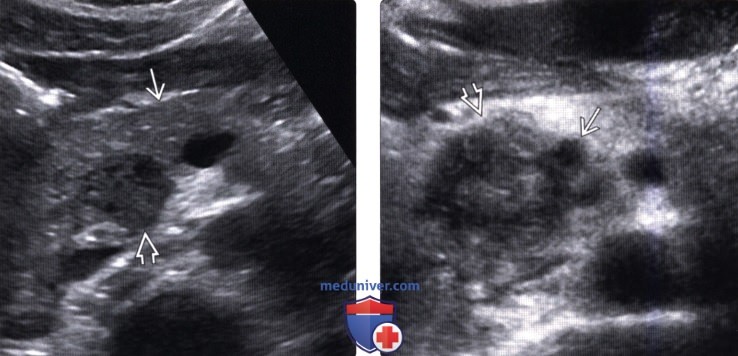

УЗИ диагностика кольцевидной поджелудочной железы: что важно знать